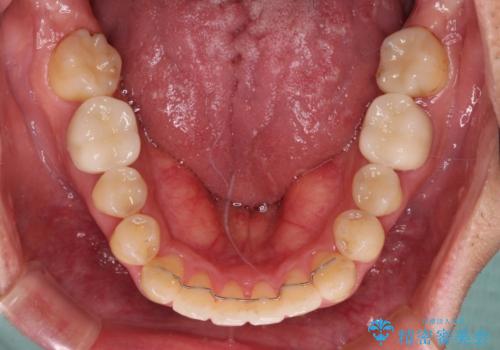

奥歯には目立つ銀歯が多くあるので、矯正治療後には下顎の銀歯をセラミッククラウンやセラミックインレーにより、補綴・修復治療することとしました。

上顎歯列全体を後方に移動させたため、口元の突出感も改善され、装置を外してからは口が閉じやすくなりました。

また、上下犬歯が接触するようになったため、奥歯にストレスのかからない歯ぎしりができるようになり、顎の疲れも改善されました。